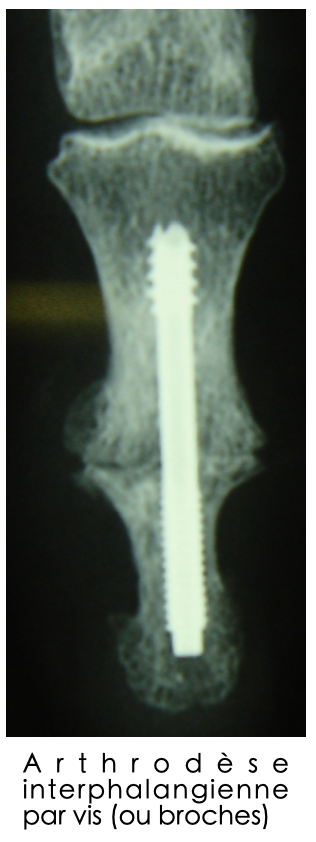

Arthrodèse interphalangienne par vis (ou broches)